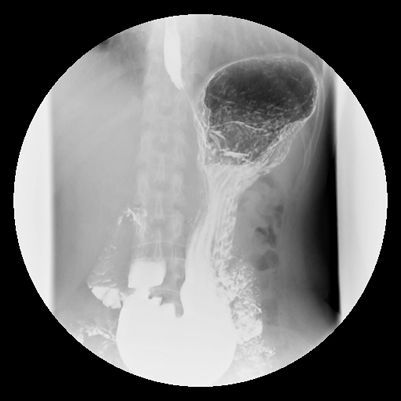

左後斜位(LPO)

胃底部充滿鋇劑。

體部、幽門充滿空氣。

十二指腸球部偶爾會充滿空氣。n

前後位(AP)

胃底充滿鋇劑。